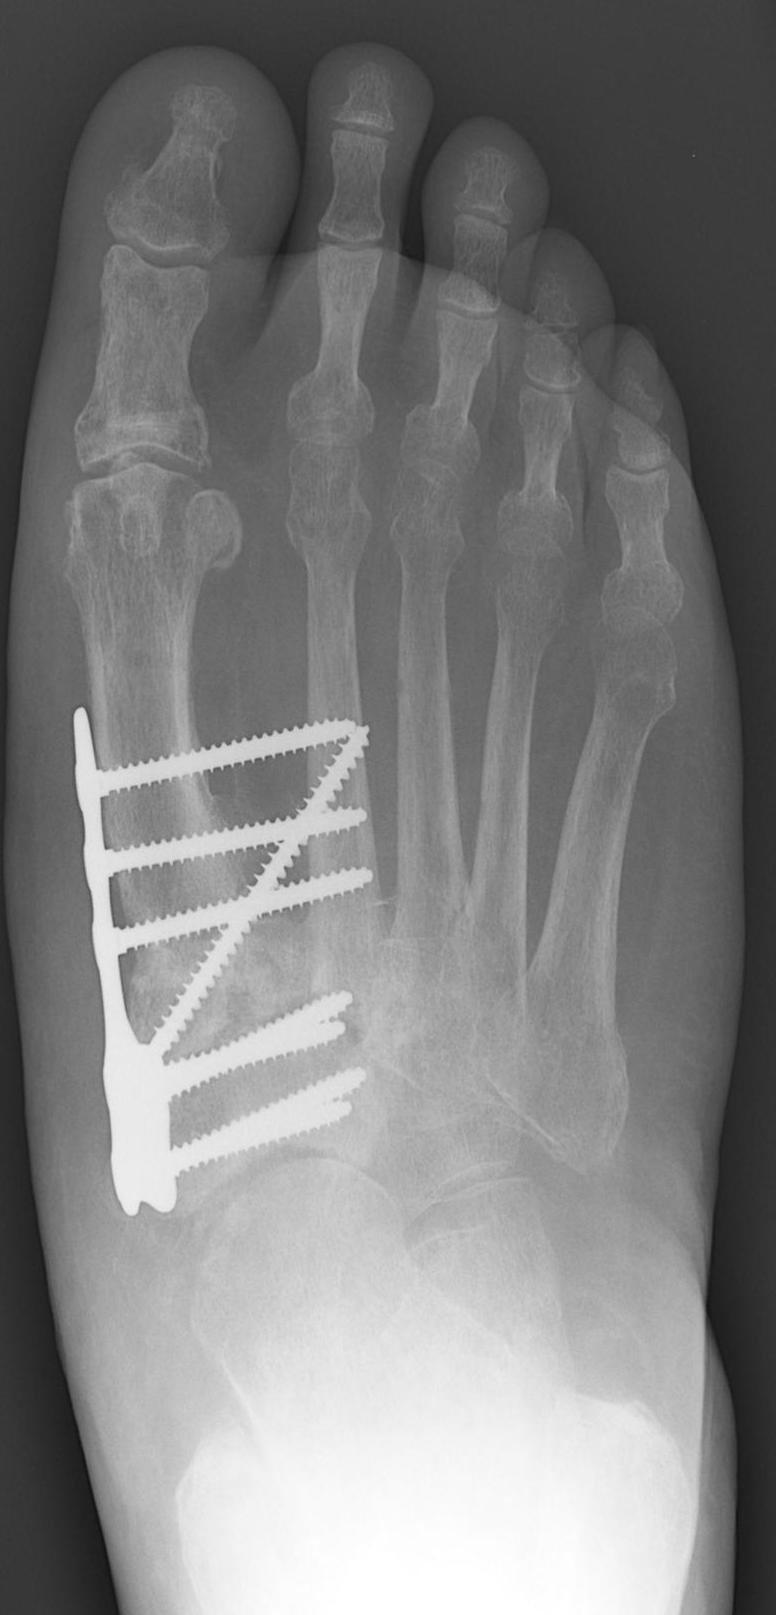

Charcot Fractures Drwolgin Foot Disease Charcot named for a 19th century french neurologist, charcot foot is a rare and potentially debilitating condition that affects the structure and. charcot foot, a condition formally known as charcot neuropathic osteoarthropathy, is an insidious invader of the foot’s structural integrity. charcotfot, längre benämnt charcots neuroosteoartropati, är en akut inflammatorisk sjukdomsprocess som drabbar fotens leder och. charcot. Foot Disease Charcot.

Charcot Foot, Xray Photograph by Science Photo Library Pixels Foot Disease Charcot charcot foot is a condition causing weakening of the bones in the foot that can occur in people who have significant nerve damage (neuropathy). named for a 19th century french neurologist, charcot foot is a rare and potentially debilitating condition that affects the structure and. charcot foot, also called charcot arthropathy, is a disease that attacks the. Foot Disease Charcot.

Figure 1 from Surgical treatment of cavus foot in CharcotMarietooth Foot Disease Charcot charcotfot, längre benämnt charcots neuroosteoartropati, är en akut inflammatorisk sjukdomsprocess som drabbar fotens leder och. most foot problems that people with diabetes face arise from two serious complications of the disease: charcot foot, a condition formally known as charcot neuropathic osteoarthropathy, is an insidious invader of the foot’s structural integrity. charcot foot is a condition causing. Foot Disease Charcot.